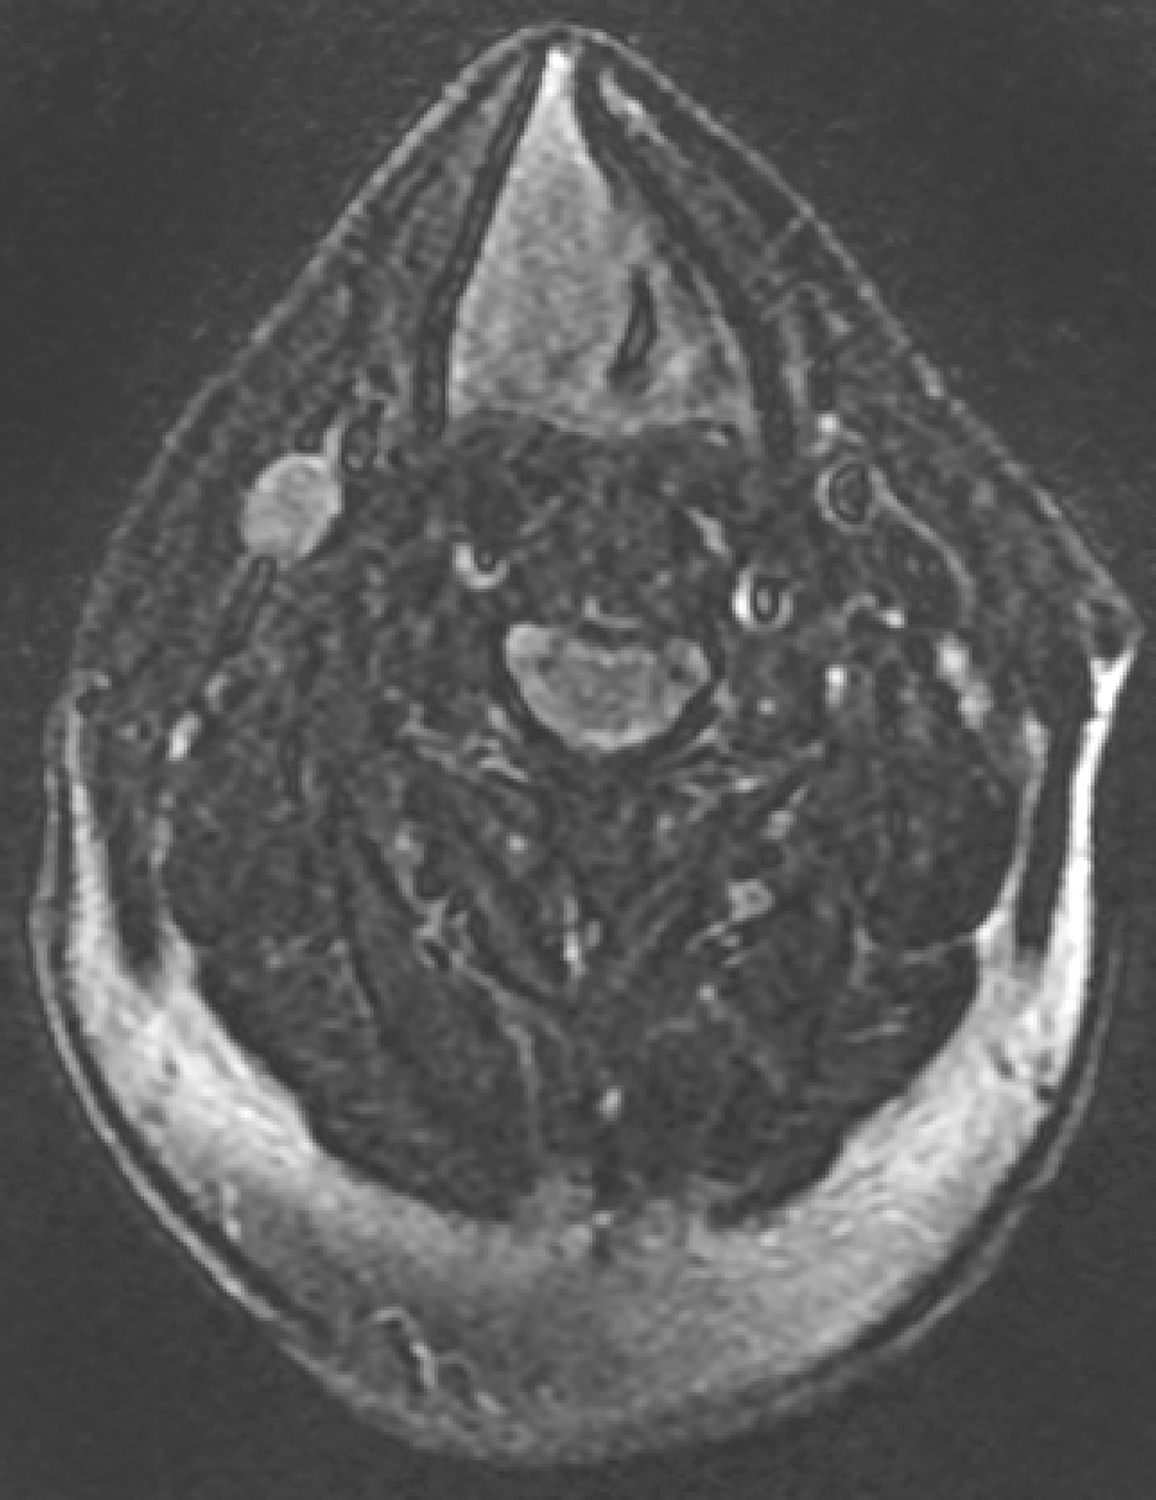

1.2017年5月25日电子鼻咽喉镜检查 内镜所见:“喉癌术后1月余”,鼻腔内镜勉强通过。鼻咽部结构完整,黏膜光滑,未见明显异常。口咽双侧扁桃体未见肿大。舌根部淋巴滤泡增生。喉腔全切除,下咽部黏膜充血,未见明显肿瘤征象(图7)。

图7全喉切除术后

引自:头颈部肿瘤多学科诊疗病例精选.第1版.ISBN:978-7-117-27929-1.主编:李正江

内镜诊断:喉癌术后,全喉切除术后改变,未见明显肿瘤征象。

2.2017年5月26日颈部下咽喉MRI增强扫描 检查所见:

(1)扫描范围内气管造瘘术后,喉部呈术后改变,局部软组织增厚、肿胀,喉腔消失,增强扫描尚均匀强化,未见明显肿物。

(2)双侧颈部呈术后改变,颏下可见淋巴结,短径约0.6cm,建议随诊。